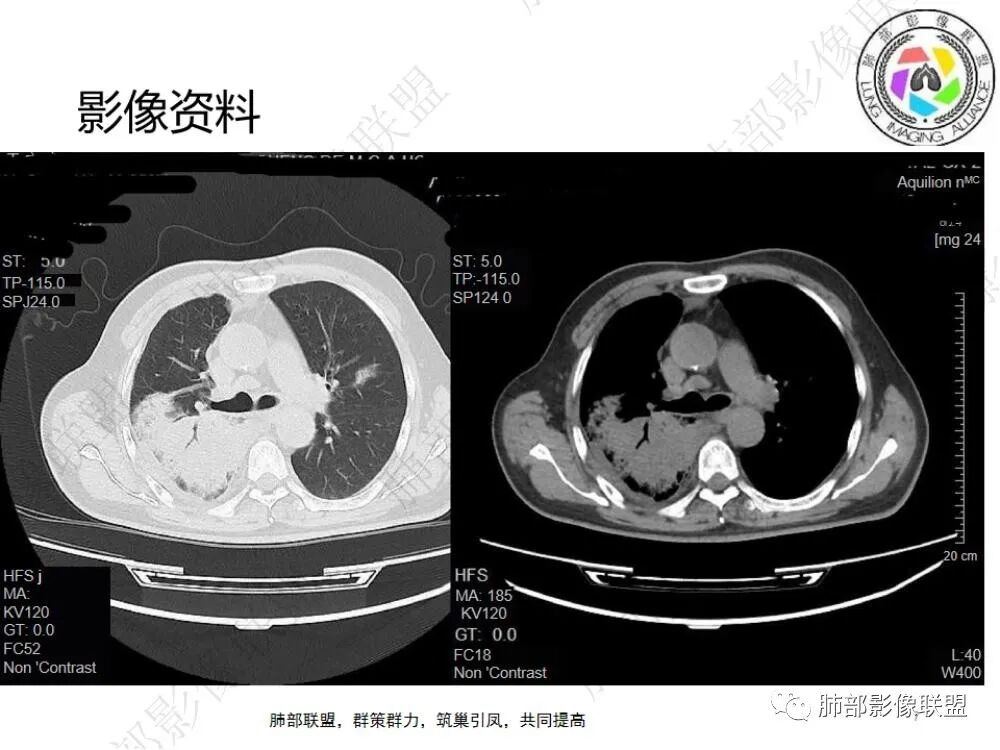

刘波:

中老年男性,发热,咳痰10天,加重5天,糖尿病病史,要考虑到糖尿病合并肺部感染四大金刚(金葡菌、毛霉菌、结核、肺炎克雷伯杆菌),C反应蛋白及白细胞明显增高,PCT增高至44.34,这个至可以考虑到脓毒症(尤其阴性菌)。2023-1-5日片,双肺多发斑片状/片子密度增高影,边缘相对较清晰/膨隆,右肺较明显,病灶内见支气管影,小支气管未见明确现实;病灶似有重力依赖,背侧明显较实,右侧胸腔见散在包裹性积液;2023-1-12,间隔一周,包裹性积液改变增多,右肺中叶外压行膨胀不全;右肺下叶病灶明显液化坏死,可以考虑肺克可能大。

1.中年男性,发热咳嗽10天,加重伴呼吸困难5天。

既往糖尿病病史,血糖控制情况不详。未提供患者一般情况,如体温血压等等。

实验室炎性指标升高,如:C-反应蛋白260.88mg/L;PCT44.34ng/L;白细胞及中性显著升高等等。

2.影像显示右肺上叶后段及右肺下叶较大范围实性密度为主片状影,边界可分辨,密度较均匀,隐约见小范围低密度(可疑液化区),未见钙化及气囊影。

3.左肺上叶见小片影,边界不清,实性及磨玻璃混合密度。

4.右侧胸腔积液,多包裹局限。

5.纵隔见轻度增大淋巴结。

6.一周后复查变化较为明显。肺部实变影有所吸收,但胸腔积液增加明显,包裹于侧胸壁、纵隔旁及叶间裂。注意右肺下叶因积液推压明显(可惜未能提供薄层图片及矢状位图片)。

7.扫描范围内肝顶叶未见异常低密度区。